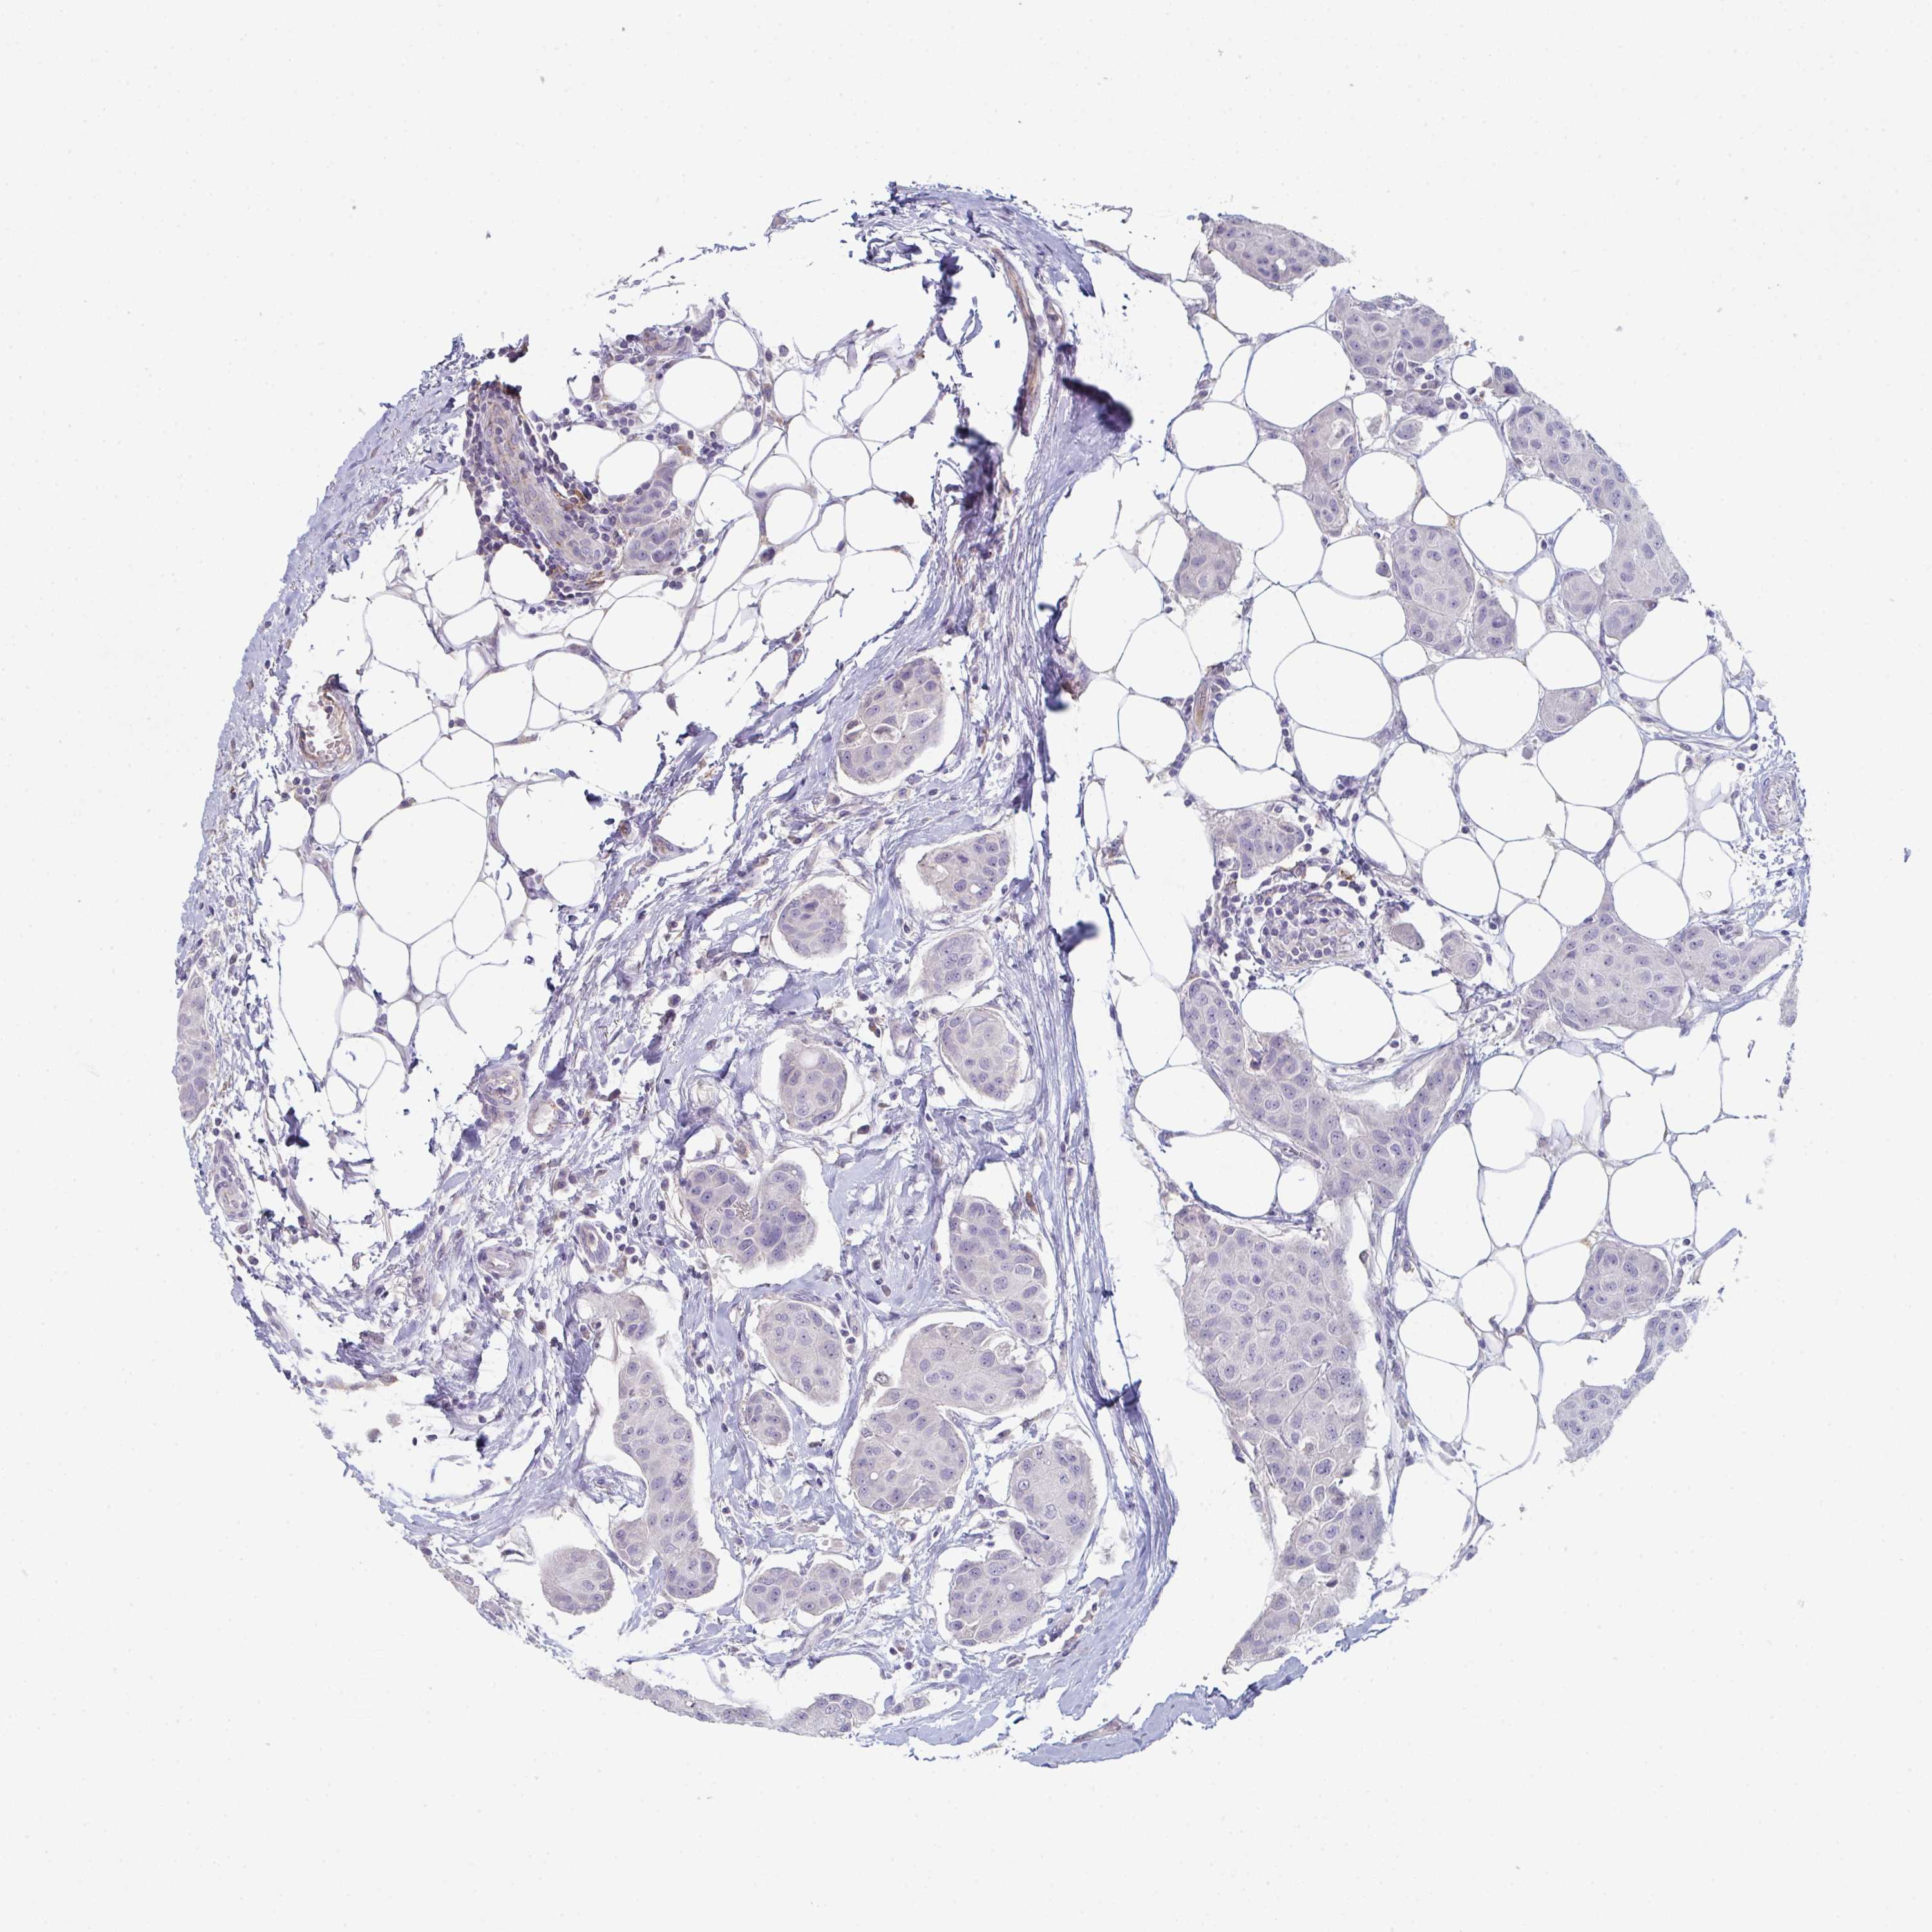

BRCA TCGA BRCA VALIDATION PROTEIN EXPRESSION

ANTIBODIES

AND

VALIDATION